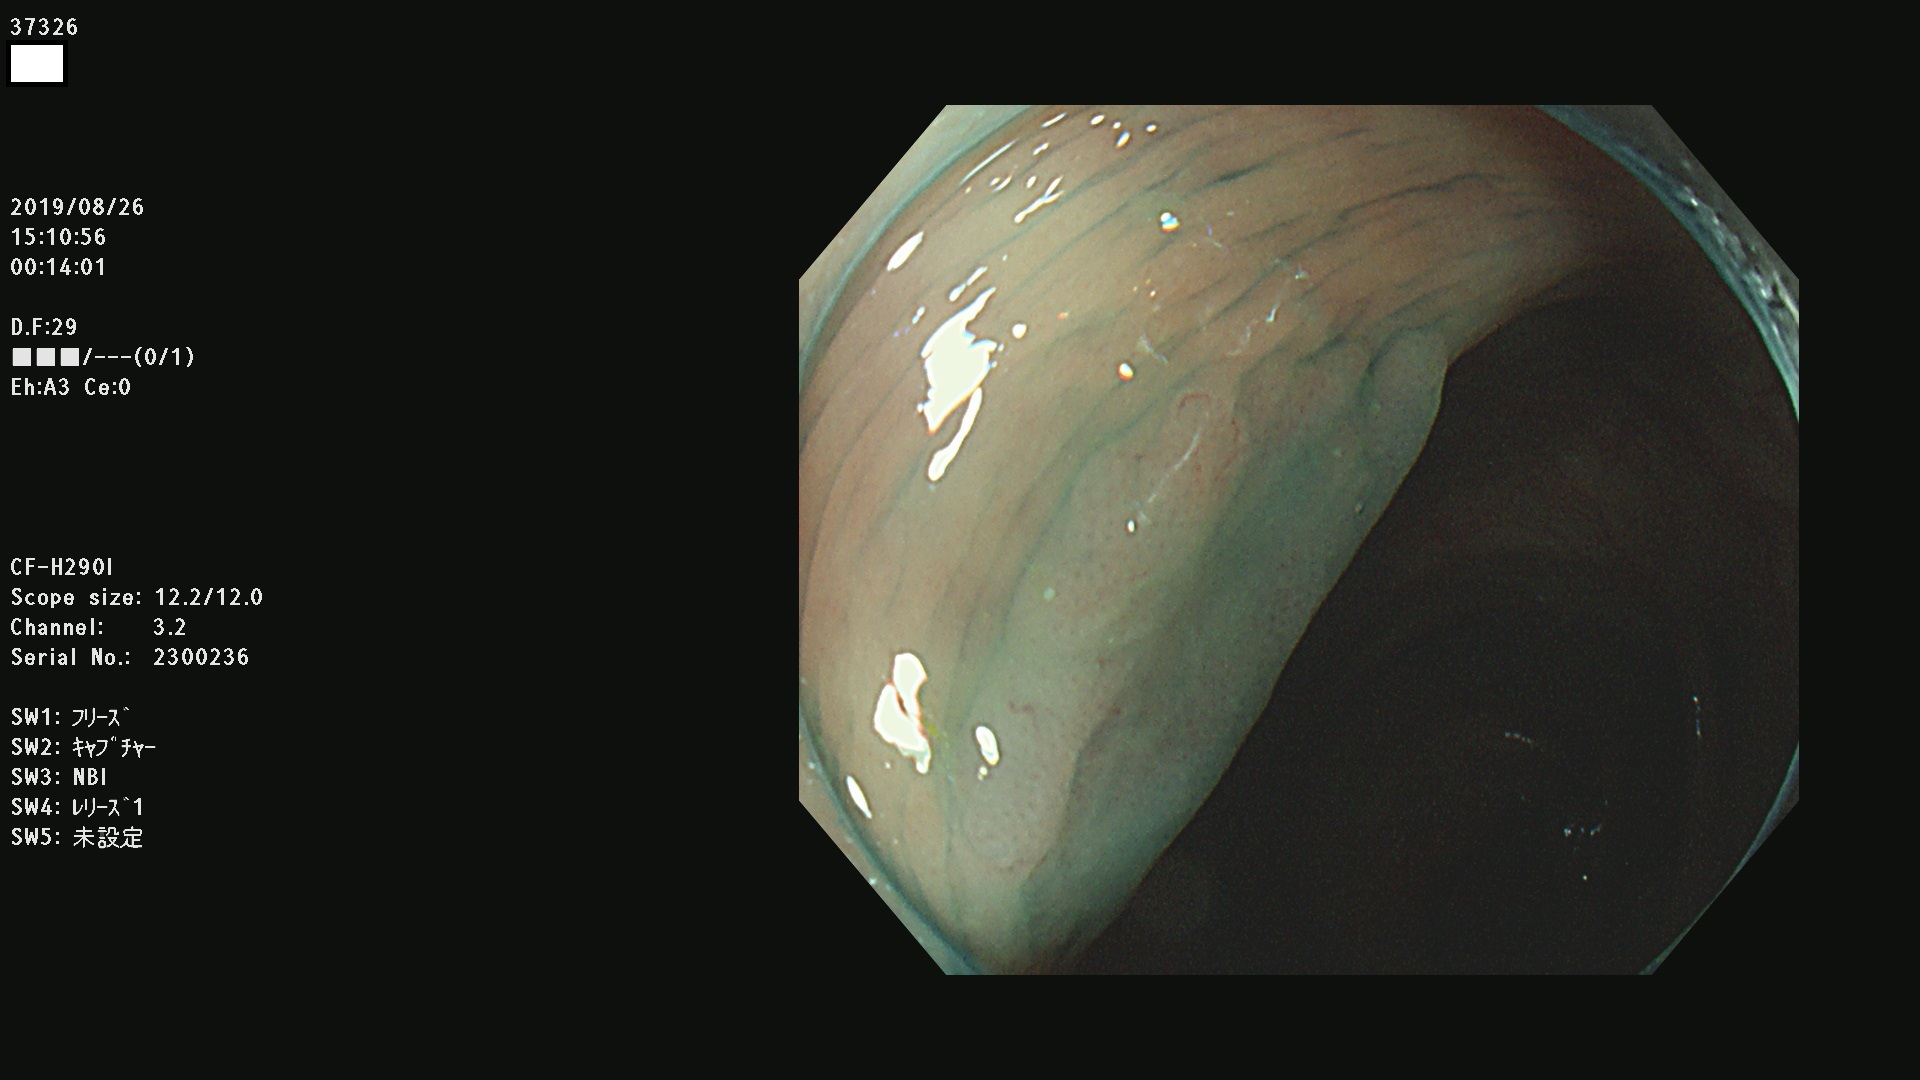

37300(SSAPのみ) 37301 37303 37304 37306 37307 37308 37309 37312 37313 37315(SSAPのみ) 37316 37317(SSAPのみ) 37319 37321(SSAPのみ) 37322 37323 37324 37325 37326 37328(SSAPのみ) 37329 37330 37331 37332(SSAPのみ) 37333 37334 37336 37337 37338 37340 37342 37343(SSAPのみ) 37344 37345 37346 37347 37348 37352(SSAPのみ) 37353 37354 37355 37356 37358 37360 37361(SSAPのみ) 37362 37363 37366 37367 37369 37370 37371 37372(SSAPのみ) 37375 37376 37377 37380 37381(SSAPのみ) 37382 37383 37384 37385(SSAPのみ) 37386 37387 37388 37389 37390 37392(SSAPのみ) 37393 37394 37395 37396(SSAPのみ) 37397 37398(SSAPのみ) 37399

発見困難で危険性の高い平坦型病変(上記100名より抽出) )